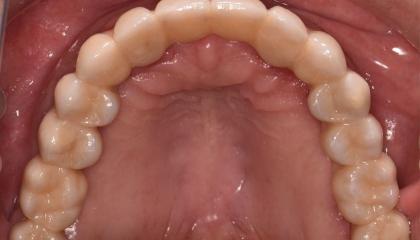

Zirconia bridge on Southern DC Implants

Tooth Replacement